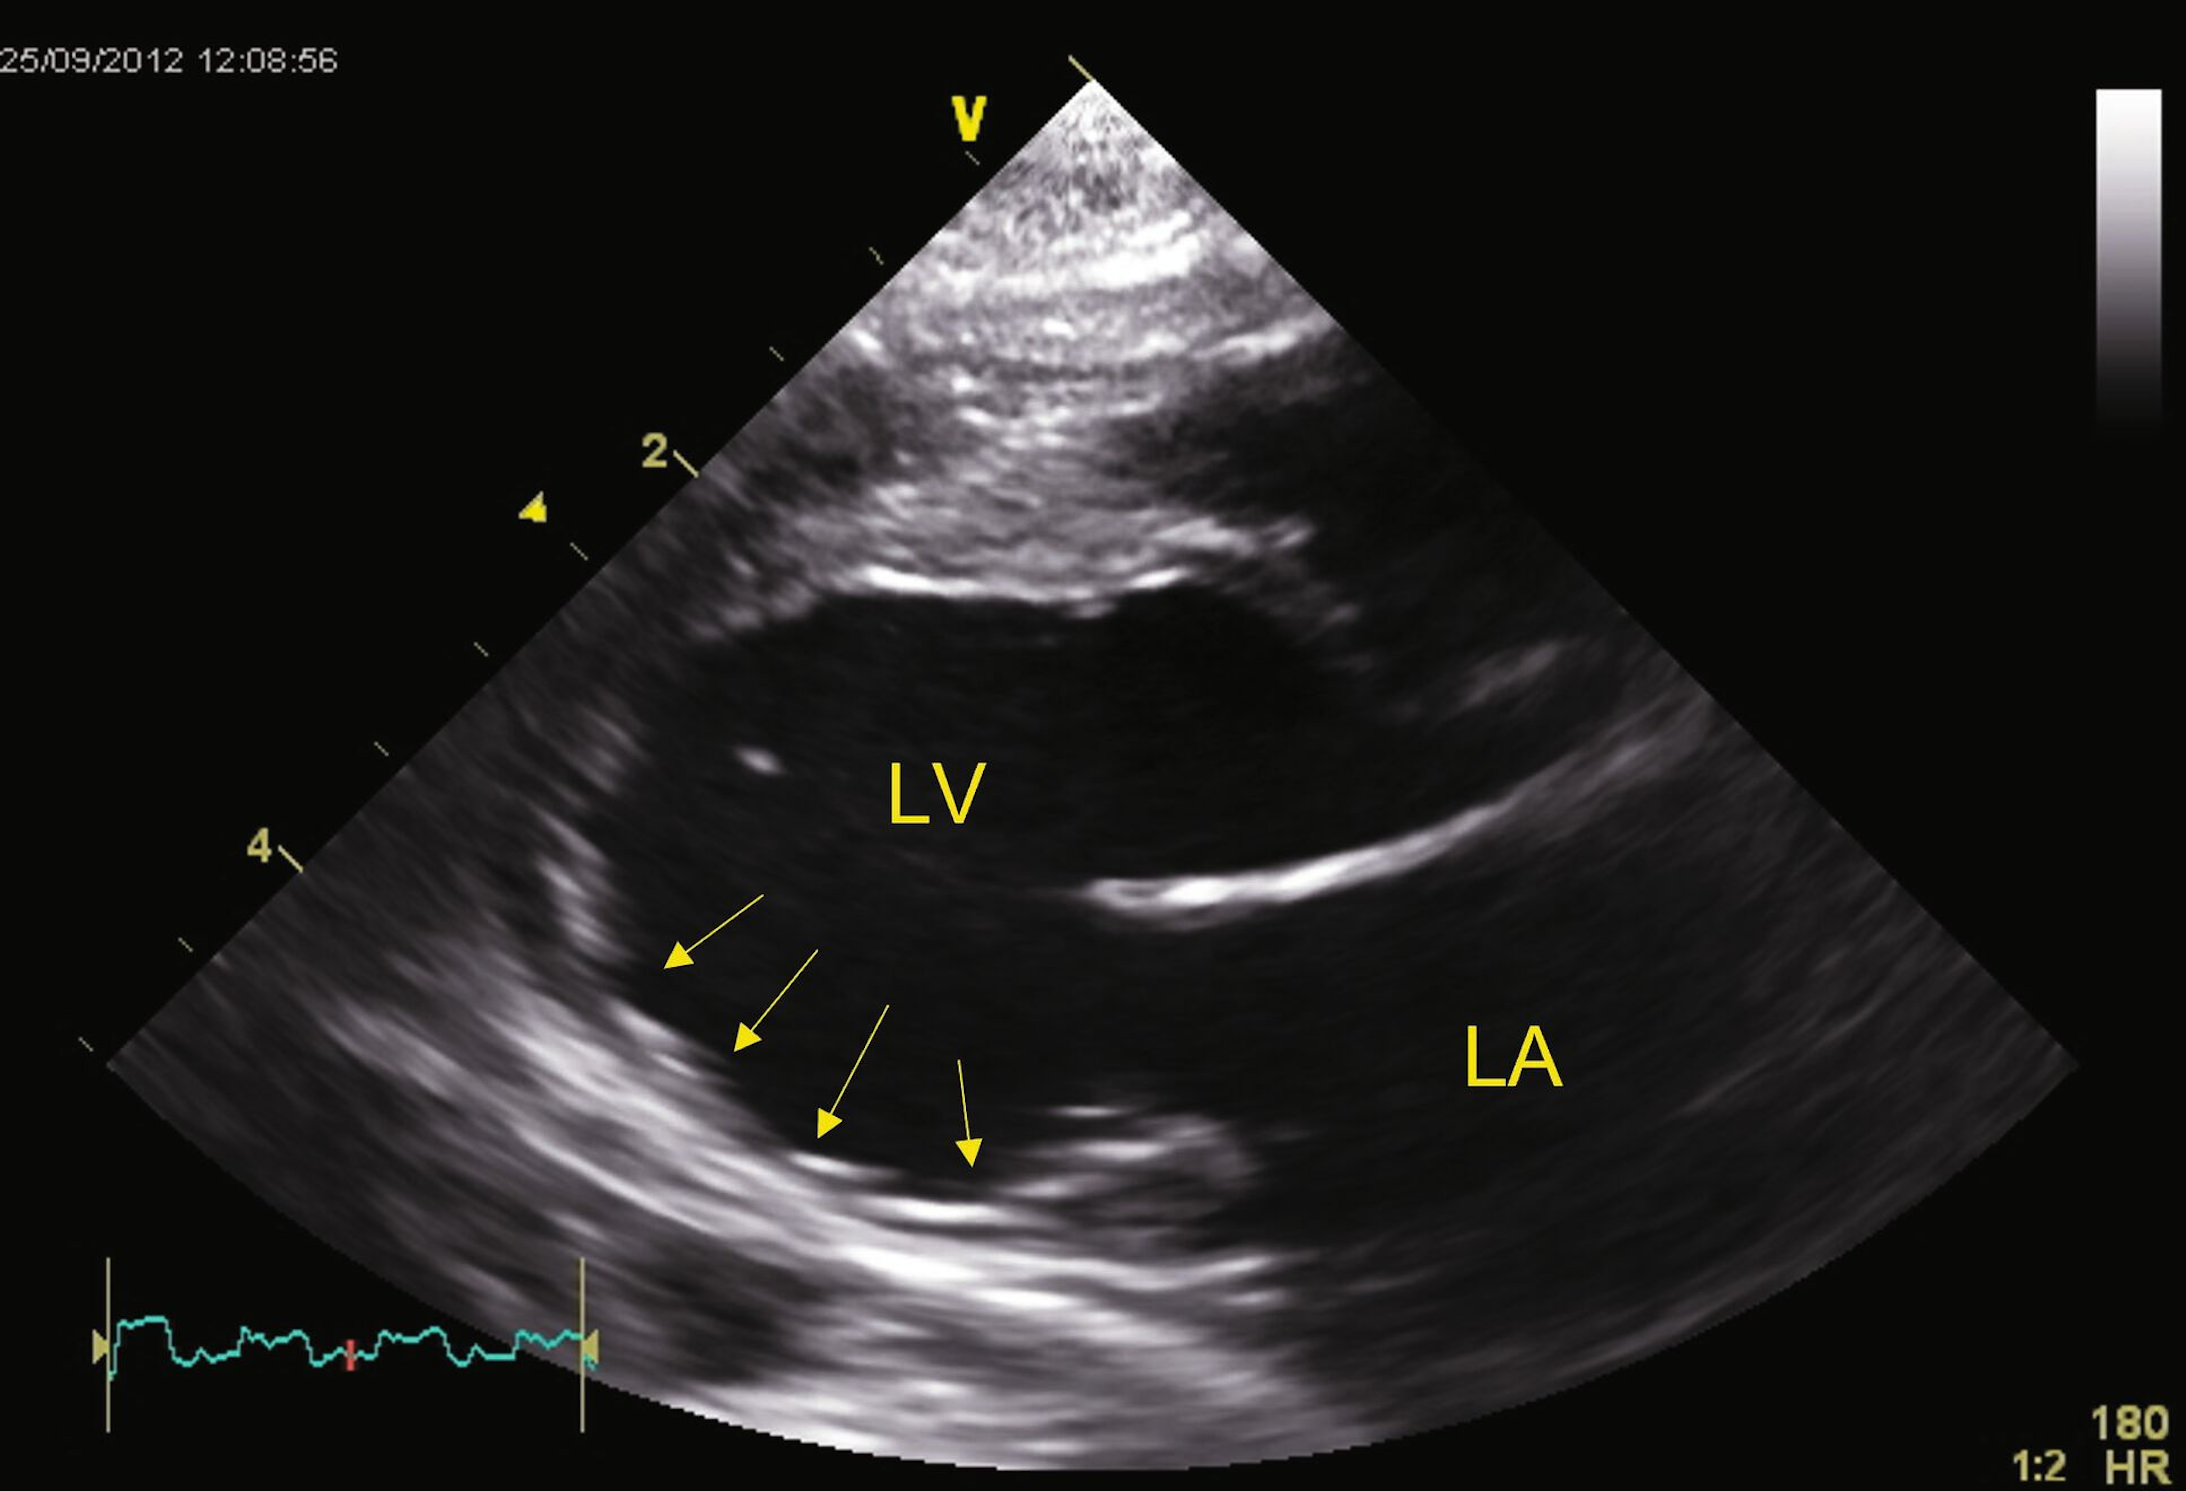

Source: parcamifc.pages.dev Cardiomyopathie hypertrophique féline au stade , Microscopiquement, le tissu cardiaque se désorganise suite à la mort des cellules myocardiques (30 à 60% des chats, 90% chez l'Homme et le. La cardiomyopathie hypertrophique du chat est une pathologie primaire fréquente qui se caractérise par un épaississement du myocarde

Source: schultzywbx.pages.dev ECG et cardiomyopathie hypertrophique — Uness Cardiologie , Il s'agit d'un syndrome regroupant de très nombreuses affections La cardiomyopathie hypertrophique du chat est une pathologie primaire fréquente qui se caractérise par un épaississement du myocarde